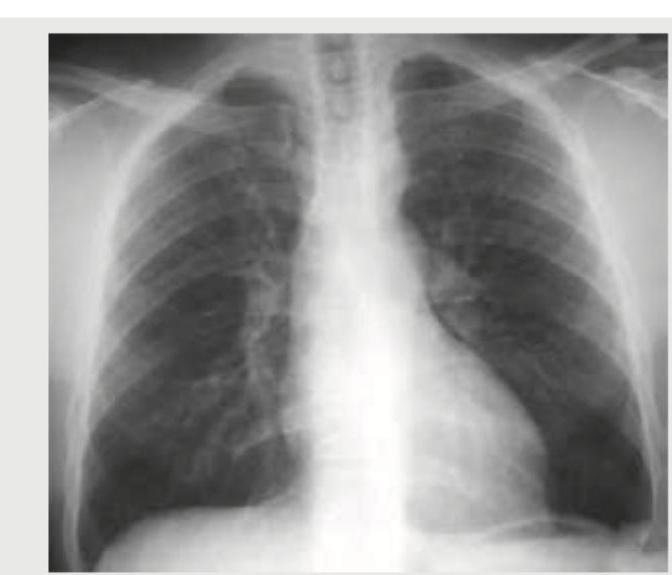

A 35-year-old hypertension patient has the following CXR in annual medical check up. What does it show?

Explanation: ***Left ventricular hypertrophy*** - The cardiac silhouette shows a **rounded left heart border** and an **increased cardiothoracic ratio**, particularly on the left side, indicating enlargement consistent with left ventricular hypertrophy. - This is commonly seen in patients with **long-standing hypertension** as the left ventricle works harder against elevated systemic vascular resistance. *Pulmonary artery hypertension* - This condition typically presents with **enlargement of the pulmonary arteries** in the hilar region, which is not prominently visible here. - While pulmonary hypertension can cause right ventricular enlargement, the image primarily suggests **left-sided cardiac enlargement**. *Coarctation of aorta* - While a cause of hypertension, coarctation of the aorta is often associated with specific radiographic findings such as **rib notching** (due to collateral vessel development) or a **'3' sign** in the aorta, none of which are evident in this image. - The image does not show a **narrowing of the aorta** or post-stenotic dilation. *Cor pulmonale* - Cor pulmonale involves **right ventricular enlargement** secondary to lung disease or pulmonary hypertension. - This would typically manifest as a prominent **right heart border** and potentially **increased retrosternal airspace** on a lateral view, which are not suggested by this frontal CXR.